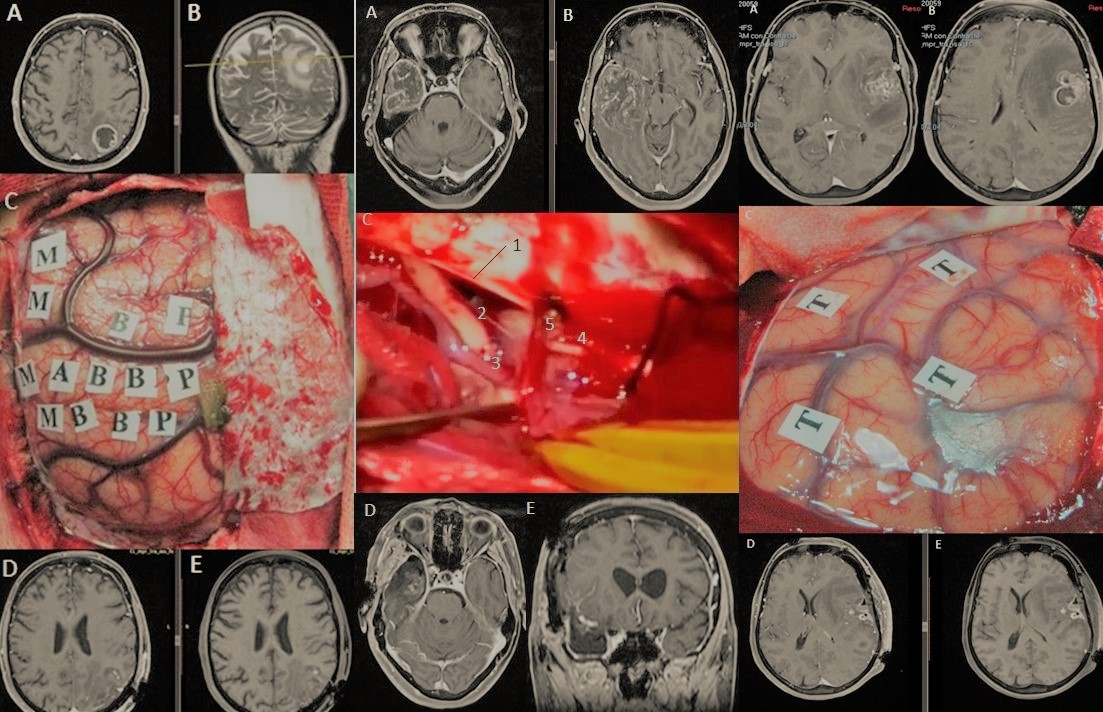

Tratamiento microquirúrgico de tumores cerebrales

3. Excelencia en la técnica microquirúrgica